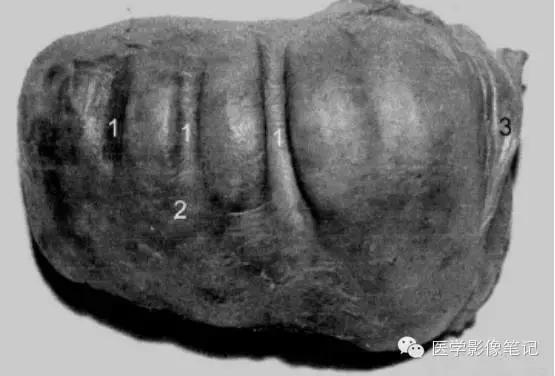

咳纹肝

女性多见,由慢性咳嗽膈肌紧勒肝脏所致,也可见于过度束腰的妇女。